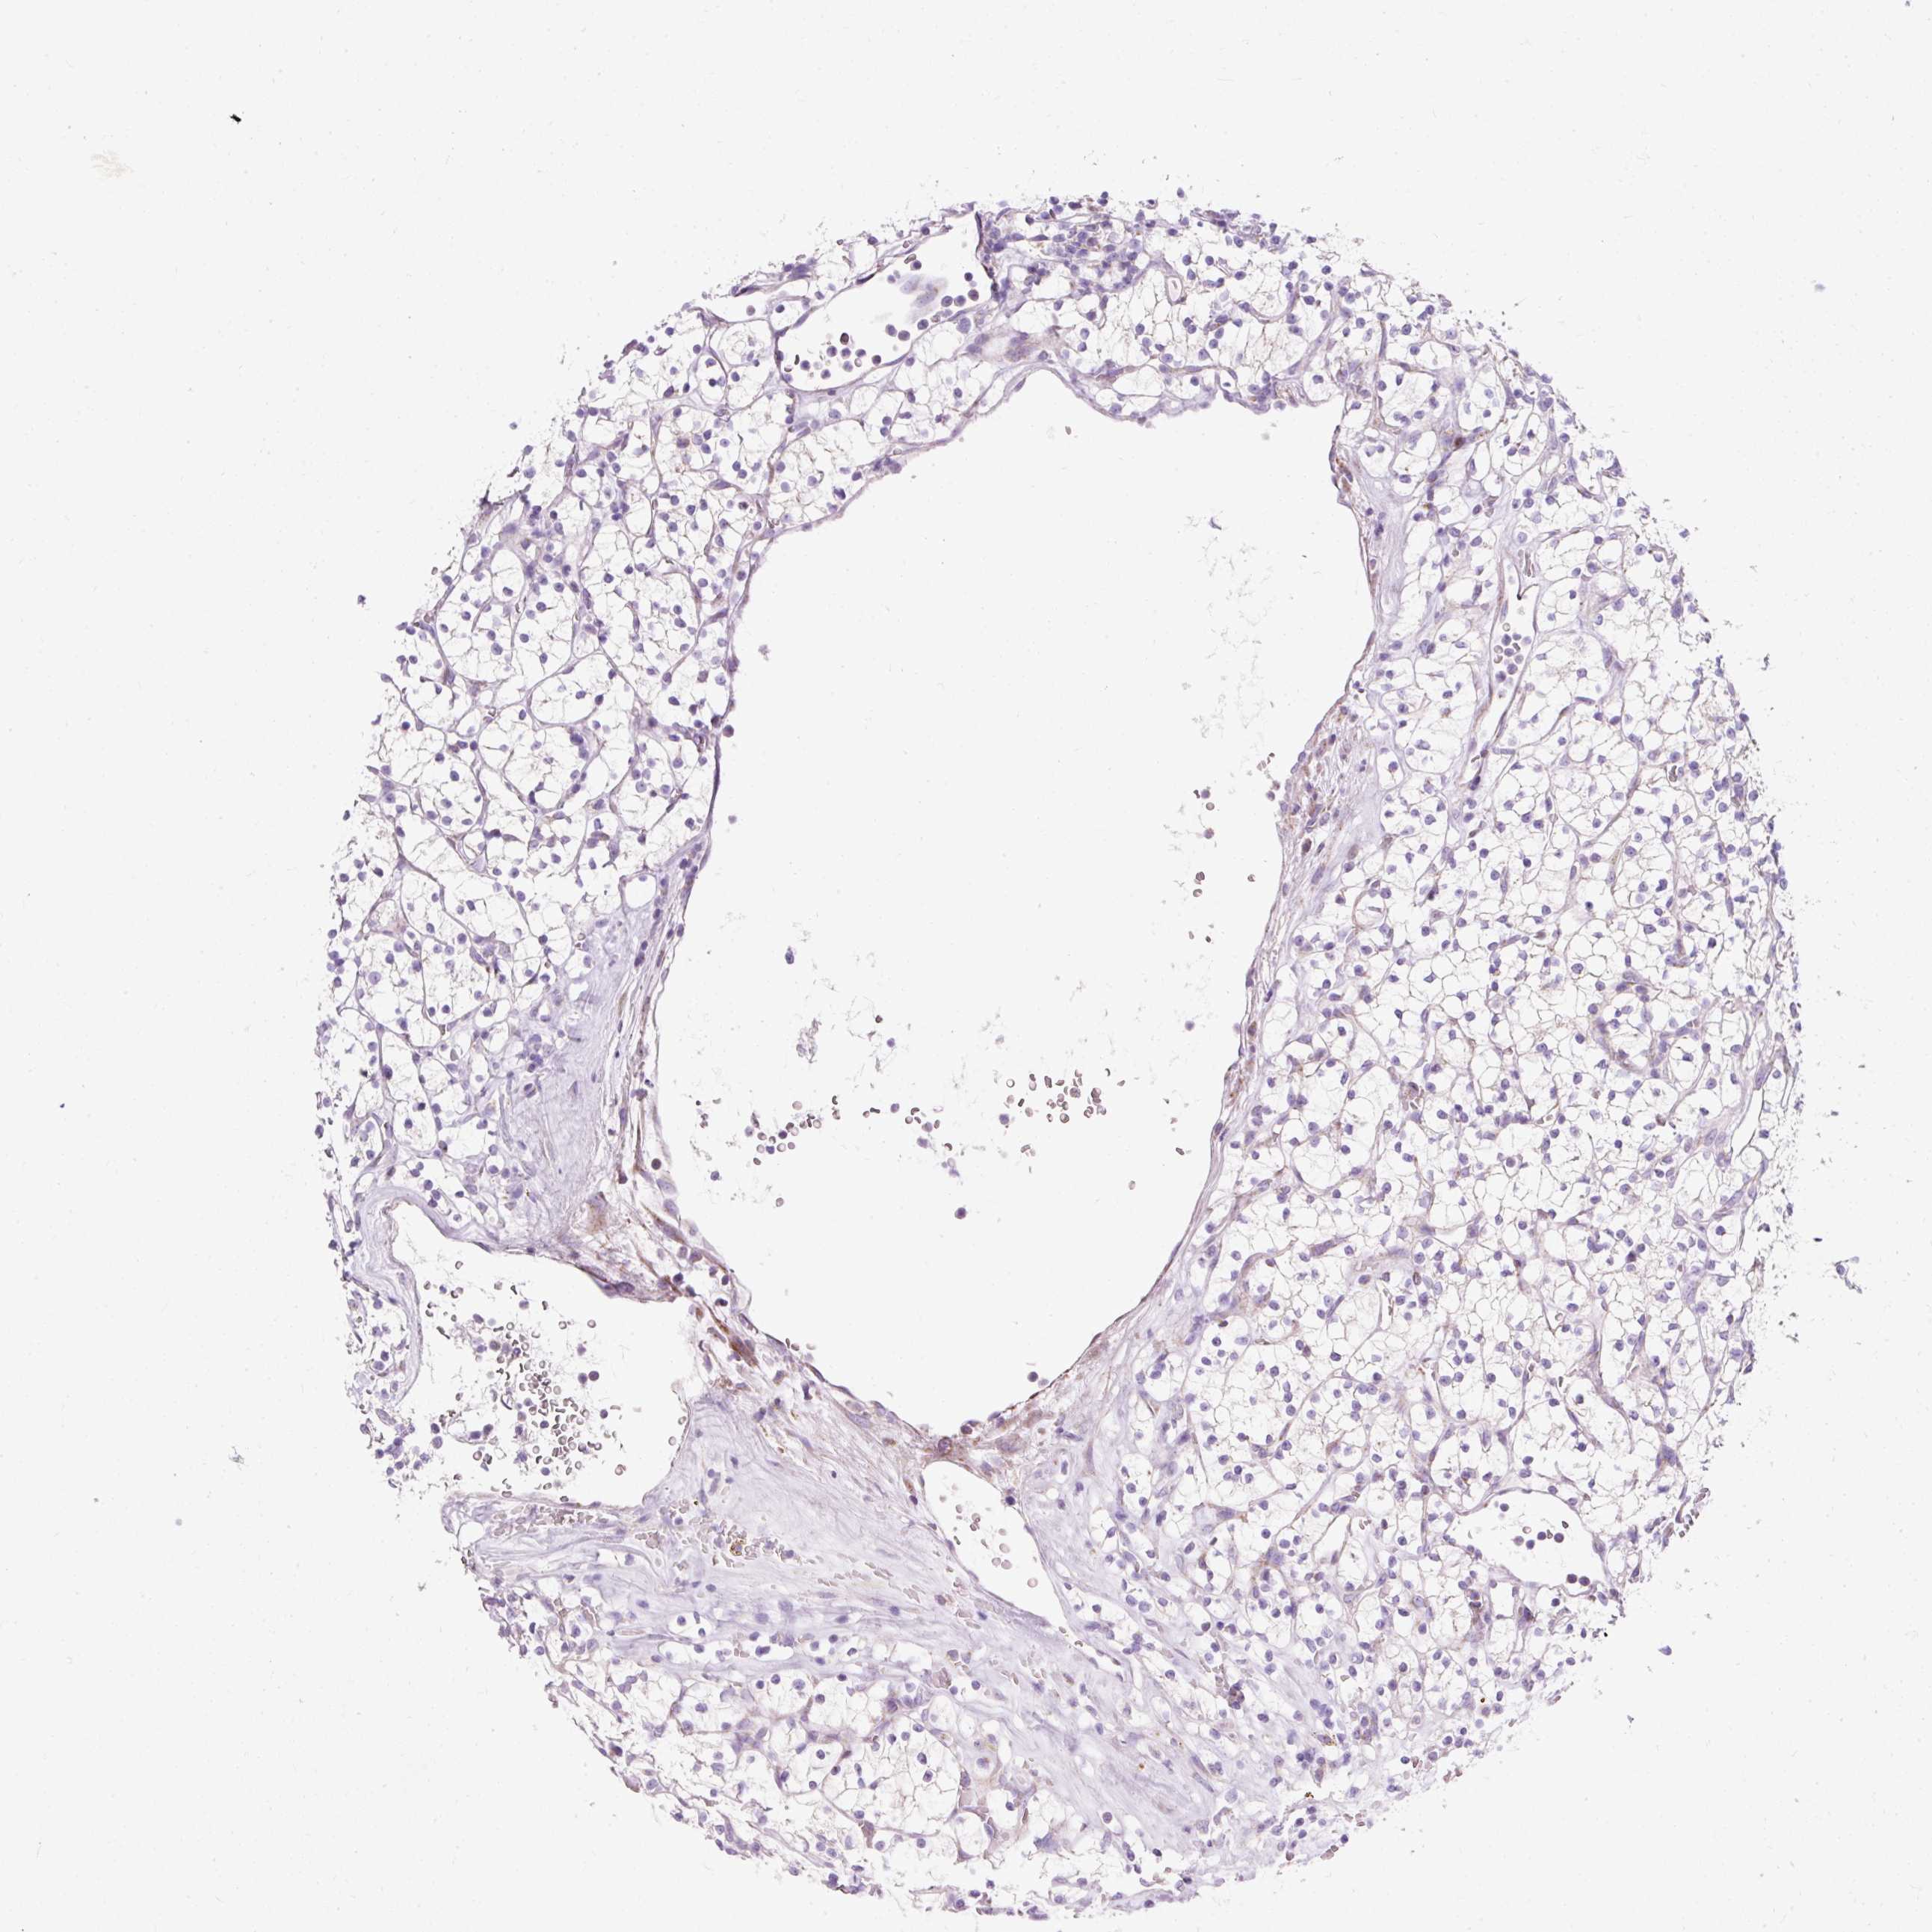

Renal cancer

Kidney chromophobe